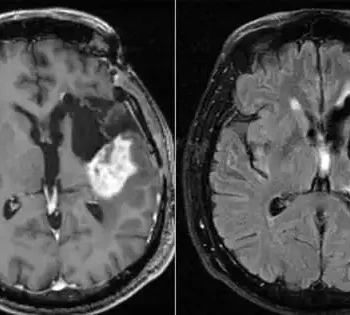

The imaging provided by an MRI scanner that is mobile and portable is referred to as portable magnetic resonance imaging (MRI). It provides MR imaging to the patient in real-time